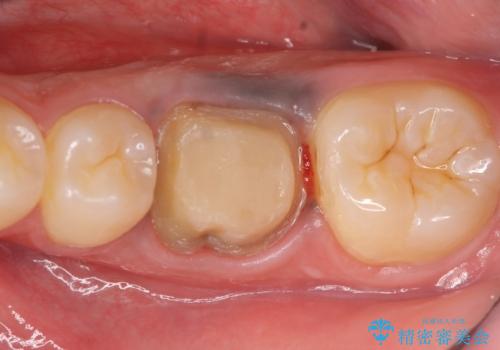

- オールセラミッククラウン…¥100,000、ファイバーコア…¥20,000、仮歯…¥10,000費用は治療当時の料金となります

今回用いたオールセラミッククラウンはジルコニアフレームという白い素材の上にセラミックを盛っているため、審美性が非常に高いのが特徴です。

また、ジルコニアは人工ダイヤモンドの材料にも使われているほど高い強度を持っており、そのためオールセラミッククラウンは審美性だけでなく、奥歯やブリッジの補綴も可能とするクラウンです。